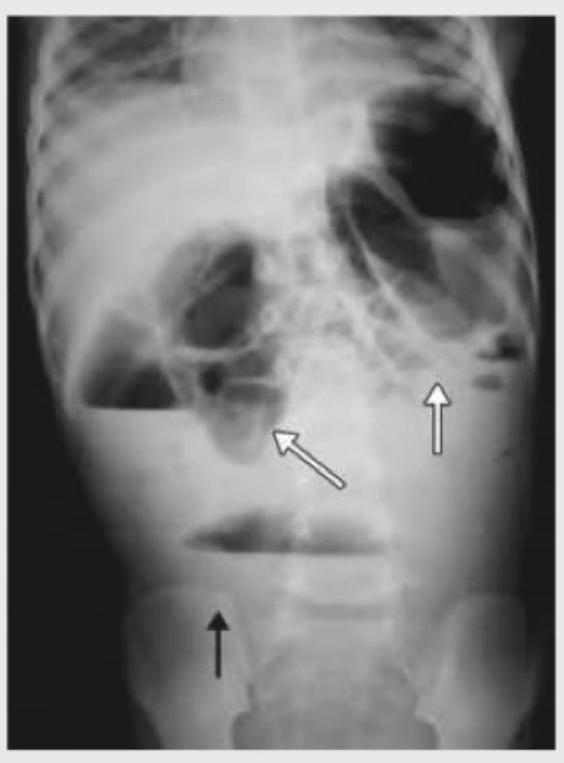

The following X-ray abdomen is diagnostic of:

Explanation: ***Perforation peritonitis*** - The X-ray image shows widespread **free air under the diaphragm** and dilated loops of bowel with **air-fluid levels**, which are classic signs of **perforation peritonitis**. - **Free intraperitoneal air** (pneumoperitoneum) is a strong indicator of a perforated hollow viscus, leading to peritonitis. *Toxic megacolon* - Characterized by **extreme dilatation of the colon** (typically >6 cm in transverse colon) with loss of haustral markings on plain film, without free air. - While it can lead to perforation, the primary finding here is *free air*, not just colitis and colonic dilation. *Intestinal obstruction* - Identified by multiple **dilated bowel loops proximal to the obstruction**, with **air-fluid levels**, and a relative absence of gas distally. - While there are dilated loops and air-fluid levels, the most prominent finding of **free air under the diaphragm** is not typically associated with an uncomplicated obstruction. *Chronic mesenteric insufficiency* - This condition involves **reduced blood flow to the intestines**, leading to chronic abdominal pain, especially postprandial, and weight loss. - Its radiographic signs are often non-specific or involve bowel wall thickening and pneumatosis, not free air or acute findings of perforation.